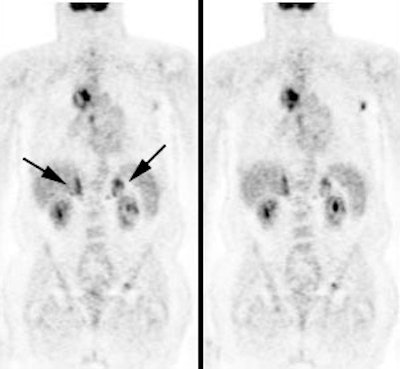

|

Change in stage: The patient below was felt to have Stage IIIB disease based upon the chest CT findings. FDG PET imaging confirmed ipsi- and contralateral mediastinal adenopathy, but also reveal a left scapular metastasis (seen retrospectively on the CT scan [white arrow]). A left iliac metastasis was also identified (black arrow right PET image). This resulted in a change in patient stage as the patient was now has Stage IV disease. |